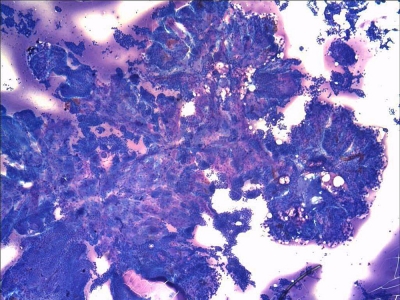

Home > MALIGNANT > Papillary Thyroid Carcinoma - Classic, Romanowsky Stain

Anastomosing true papillae.

Keywords: Papillary Carcinoma, Classic, Papillae